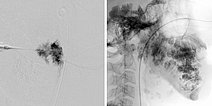

Digital subtraction angiography (DSA left; unsubtracted image right) after direct puncture and insertion of a cannula into the venous malformation during sclerotherapy.